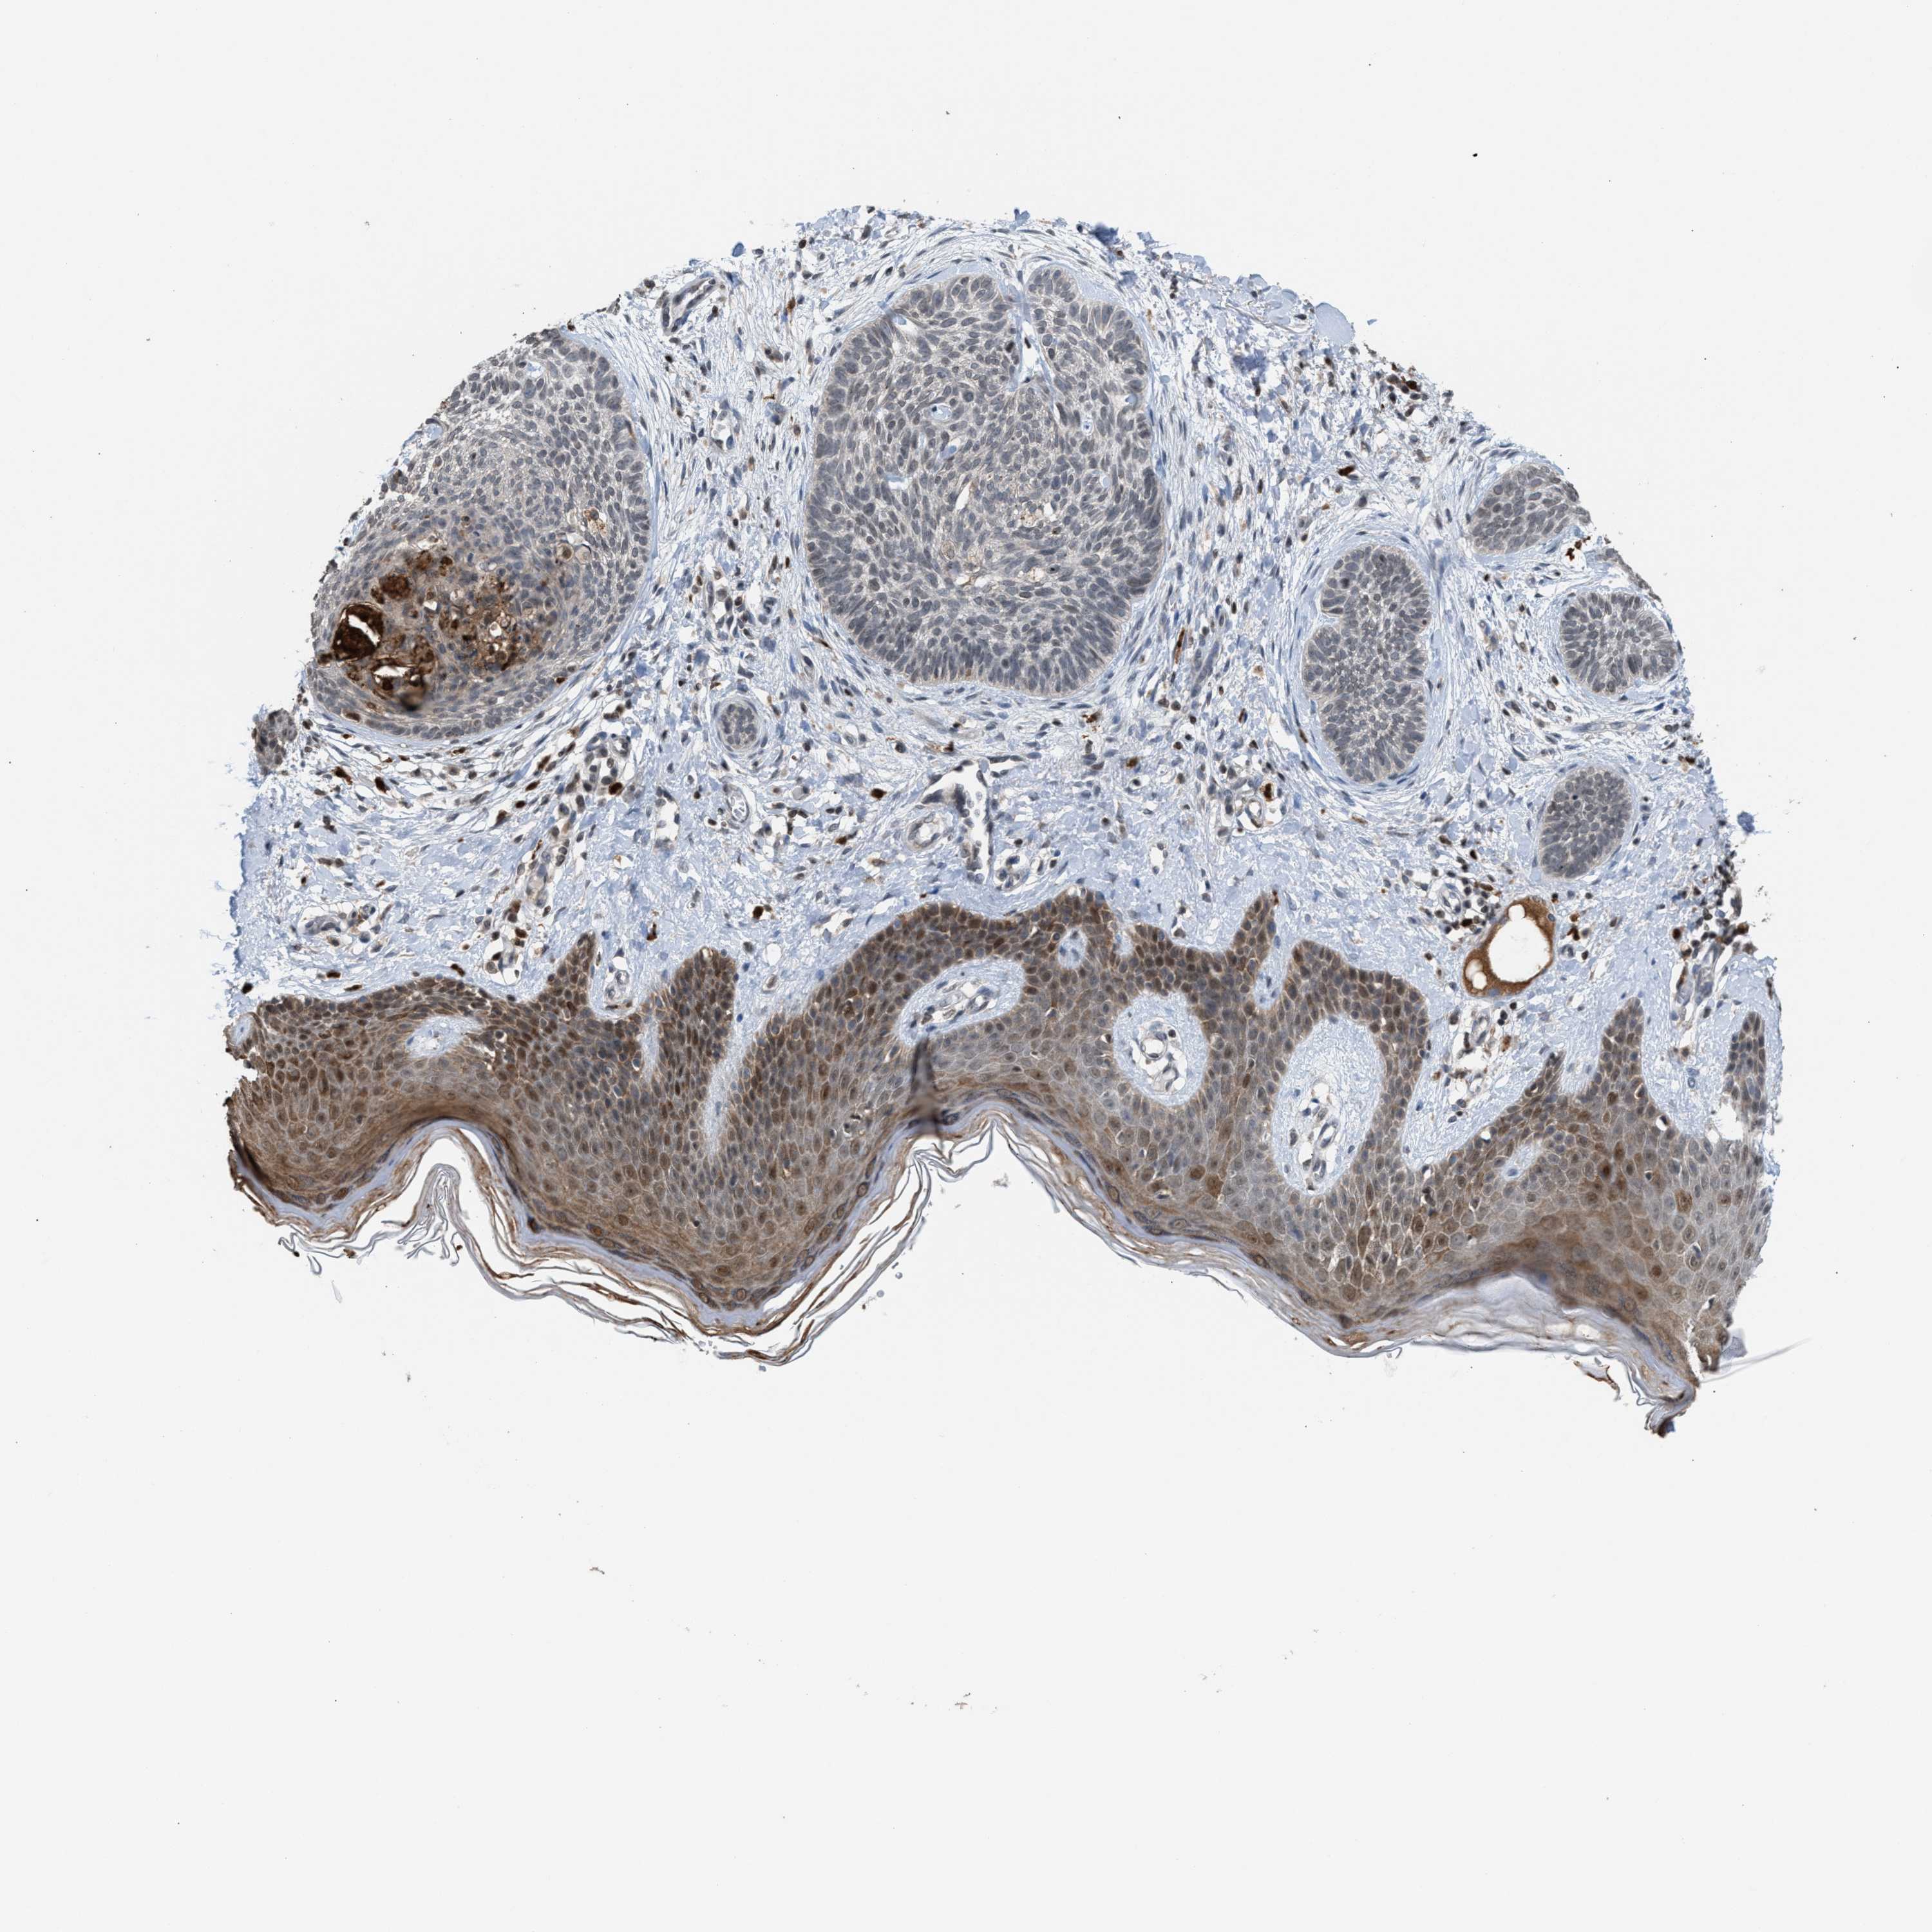

SKIN CANCER - Protein expressioni

A mouse-over function shows sample information and annotation data. Click on an image to view it in a full screen mode. Samples can be filtered based on level of antibody staining by selecting one or several of the following categories: high, medium, low and not detected. The assay and annotation is described here.

Each image is clickable and will lead to virtual microscopy that enables deeper exploration of all samples and also displays staining intensity scores, fraction scores and subcellular localization as well as patient and tissue information for each sample.

Antibody HPA031079

Staining

Low

Intensity

Weak

Quantity

<25%

Location

Cytoplasmic/membranous,nuclear

Basal cell carcinoma

Adnexal tumor, benign